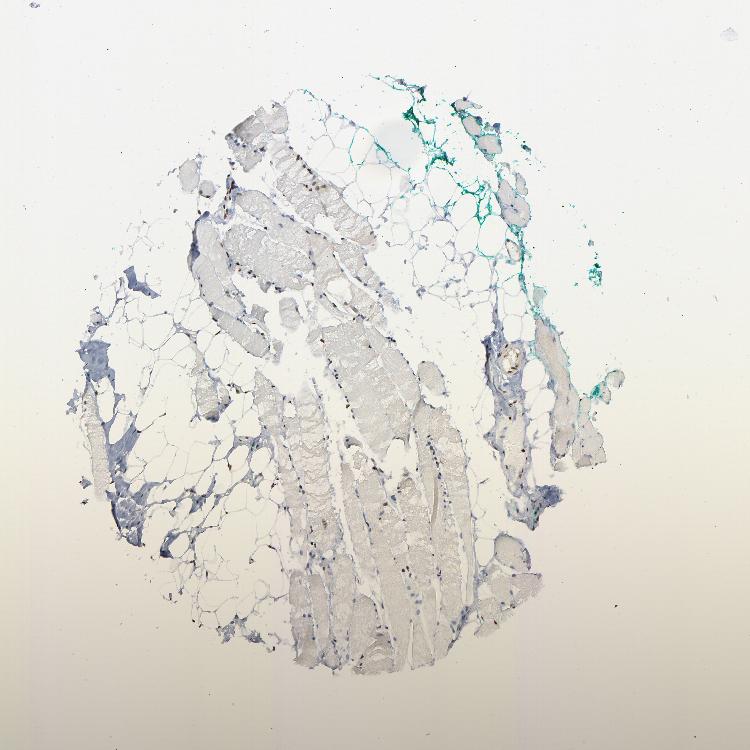

SKELETAL MUSCLE - Antibody stainingi

Antibody staining in the annotated cell types in the current human tissue is reported as not detected, low, medium, or high, based on conventional immunohistochemistry profiling in selected tissues. This score is based on the combination of the staining intensity and fraction of stained cells.

Each image is clickable and will lead to virtual microscopy that enables deeper exploration of all samples and also displays staining intensity scores, fraction scores and subcellular localization as well as patient and tissue information for each sample.

Antibody HPA019150Antibody CAB003803

Myocytes HighLow